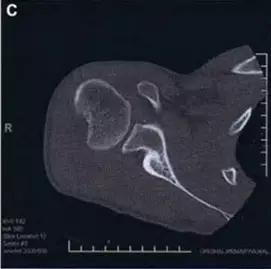

Cedell 骨折的 CT 片 (来源:Fracture of the posterior medial tubercle of the talus :A case report and review of the literature. Acta Orthop. Belg., 2007, 73, 804-806)